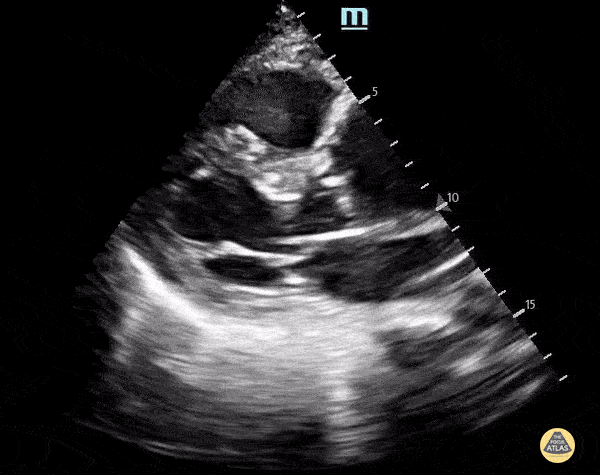

A 56-year-old with metastatic cancer presents with progressive dyspnea, chest discomfort, and fatigue. Vitals: HR 128, BP 84/56, RR 28, SpO₂ 93% RA. Exam: ill-appearing, elevated JVP, muffled heart sounds, cool extremities, clear lungs. A focused apical 4-chamber cardiac PoCUS image is shown.

What are the key ultrasound findings? What is the most likely diagnosis?

Findings: large pericardial effusion

Diagnosis: What is cardiac tamponade?